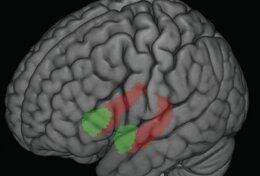

После уникального случая, который случился с одним из жителей Франции многие медики стали размышлять над вопросом, нужен ли человеку мозг? Поводом для этого послужил интересный и необычный случай с мужчиной по фамилии Матье.Ещё восемь лет тому назад в одном из французских медицинских изданий была опубликована статья, повествующая о случае, произошедшем с одним из жителей европейского государства. В ней рассказывалось о том, что в один прекрасный день в больницу пришёл человек сорока четырёх лет, который попросил избавить его от боли в левой ноге, пишет интернет-портал piterburger.ru. Медицинские работники сразу же провели углублённое обследование всего организма мужчины и установили, что спинномозговая жидкость скопилась в черепе и полностью заняла место, где должен был располагаться мозг.

Интересным есть то, что специалисты выяснили, что уровень IQ этого француза был чуть ниже среднего показателя, а мозг мужчины был настолько мал, что его даже видно на снимках не было.

Сейчас данная загадка остаётся не разгаданной. Эксперты понимают из-за чего мозг, был не большой, а вот то, как этот человек с ним жил полноценной жизнью есть странным?